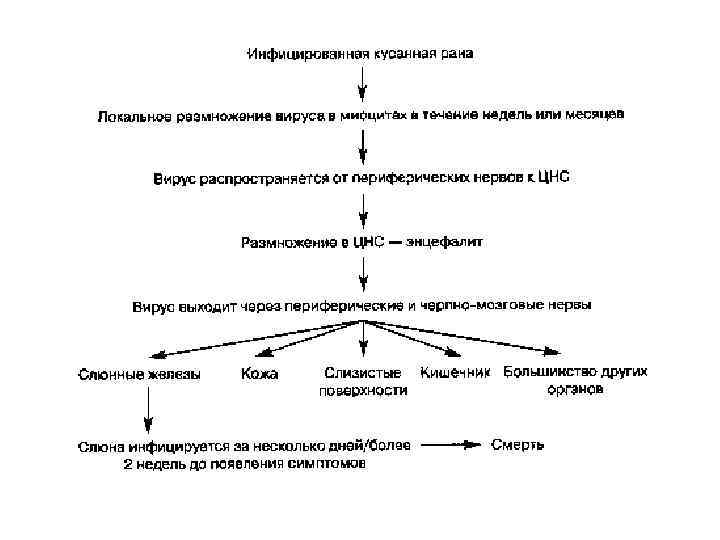

• Возбудитель проникает в организм человека через повреждённые кожные покровы или слизистые оболочки от заражённых животных при укусе или ослюнении. Центростремительно по периневральным пространствам и нервным волокнам вирус бешенства достигает ЦНС, а затем по тем же нервным стволам центробежно направляется на периферию. • Вирус способен избирательно связываться с ацетилхолиновыми рецепторами, что объясняет селективное поражение некоторых групп нейронов и приводит к повышению рефлекторной возбудимости, а затем к развитию параличей. • В головном мозге формируются отёк, кровоизлияния, дегенеративные и некротические изменения. Процесс захватывает кору головного мозга, мозжечок, зрительный бугор, подбугорную область, ядра черепных нервов.

• С изменениями в ЦНС связаны судорожные сокращения дыхательных и глотательных мышц, • повышение отделения слюны и пота, • дыхательные и сердечнососудистые расстройства. • В цитоплазме клеток мозга обнаруживают эозинофильные включения (тельца Бабеша-Негри). • В дальнейшем из ЦНС вирус попадает в различные органы и системы: скелетные мышцы, сердце, лёгкие, печень, почки, надпочечники. • Проникая в слюнные железы, он выделяется со слюной.